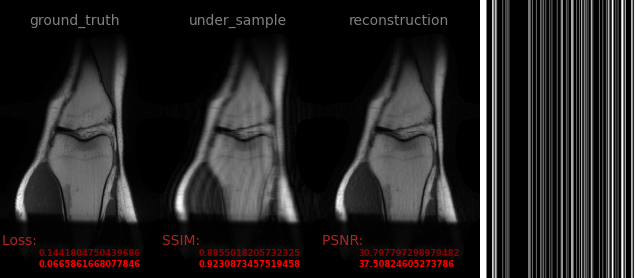

AVS-Net

Image-to-Image

medical

avs_b10

106.png